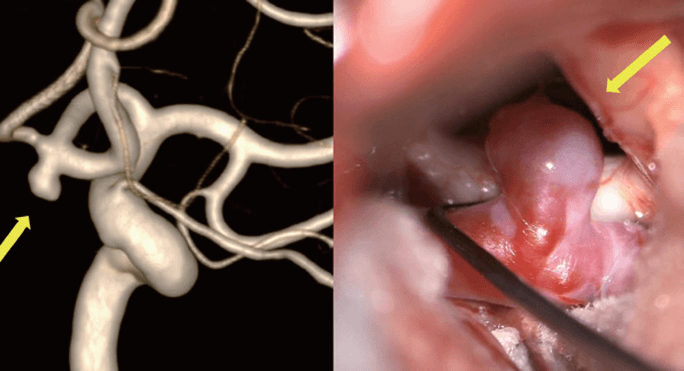

뇌혈관조영술에서 확인된 뇌동맥류(왼쪽)와 실제 뇌동맥류(오른쪽)